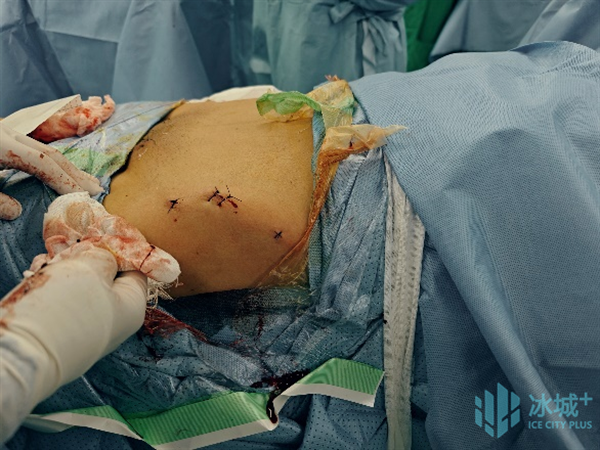

术中,刘建宇教授对复位位置及路径进行预览并确认规划后,分别将手术机械臂与患者健侧、患侧稳定固定把持,并使用电动骨科牵引架与患者下肢稳定连接,采用力-位协同控制模式进行机器人精准闭合复位,在全程多角度实时可视监控和自动规划引导下,安全完成骨盆骨折闭合复位,术中透视验证复位结果满意。最后,他操作机器人进行了螺钉通道置入规划,在实时动态三维可视化导航下,精准置入螺钉,完成了该例骨盆骨折的微创治疗。“数智化微创手术”用时2小时,患者腹部仅留有5个长度1cm的手术切口,术中出血量仅有50ml。

图6 患者手术切口